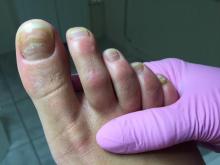

Bijgaand de nagels van een van mijn cliënten. Het gaat hier om een jonge vrouw, zij heeft maat 41 en redelijk lange tenen. Mevrouw heeft als kind met te kleine schoenen gelopen. De witte strepen overdwars lopen bij nagenoeg alle nagels op dezelfde hoogte: is hier sprake van een breuklijn, een beschadigd nagelbed, een mycose of beide? De witte strepen lijken geen oppervlakkige mycose want ik kreeg ze door middel van frezen niet weg. De nagels zijn dun en ik wilde niet verder frezen om splijten te voorkomen; de witte strepen zitten diep in de nagelplaat en lijken fijner van structuur dan de gele verkleuring. De gele verkleuring (waarvan mijn vermoeden een mycose is) liet zich wel goed verwijderen.

Hartelijk dank voor het meesturen van de foto’s. Het is altijd moeilijk om een juiste diagnose te stellen van een foto. Maar hier lijkt sprake van Leuconychia transversa. Deze aandoening die kan ontstaan als een reactie op een trauma (bv door te kleine schoenen), kenmerkt zich door witte, dwarslopende, banden over de nagelplaat. Er zijn ook andere reden voor het ontstaan van leuconychia transversa zoals bijvoorbeeld chemotherapie, infecties, (acute) stress. Leuconychia transversa kan ook erfelijk zijn.

De nagel van de hallux van de linkervoet betreft een stootnagel. Hier is mogelijk een trauma van de hallux aan voorafgegaan. Het is zinvol om samen met jouw cliënt na te gaan wat de mogelijk oorzaak is van het ontstaan van de leuconychia. Zijn de huidige schoenen adequaat? Draagt mevrouw adequate kousen/sokken? Sport mevrouw en zijn de sport en/of de sportschoenen mogelijk de oorzaak voor het ontstaan van de nagelbeschadigingen? Is mevrouw behandeld tegen kanker? Heeft mevrouw een neurologische aandoening, een vaataandoening of andere aandoening? Gebruikt mevrouw medicatie?

Of hier ook sprake is van een onychomycose, is op basis van de foto’s niet te zeggen. Hiervoor zal een biopt moeten worden afgenomen. Het vermoeden bestaat dat er eerder sprake is van overmatige mechanische stress op de nagelplaat waardoor deze problemen ontstaan.